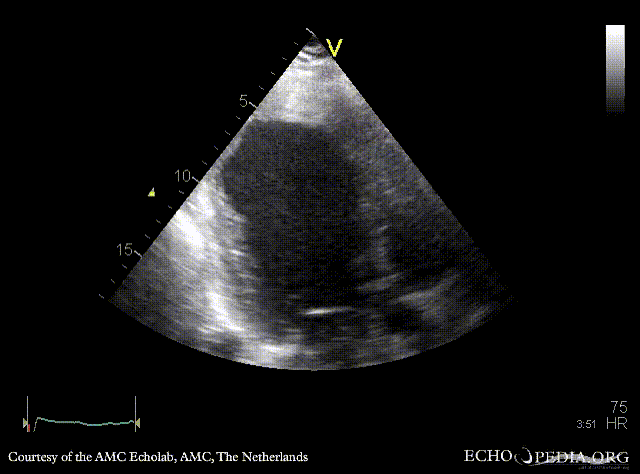

Thrombus in the apex of left ventricle

Courtesy of: AMC Echolab, AMC, The Netherlands

A4CH: dilated left ventricle, poor function, large thrombus in the apex, spontaneous echocontrast A2CH